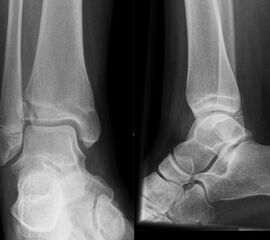

Übergangsfrakturen

Übergangsfrakturen sind spezielle Verletzungen, die ausschließlich in der Lebensphase beobachtet werden, in welcher die Wachstumsfugen teilweise geschlossen sind. Die Wachstumsfuge an der distalen Tibia schließt sich von ventromedial beginnend nach dorsal und lateral. Während die bereits geschlossene Wachstumsfuge eine hohe Stabilität aufweist, ist der knorpelige Anteil der noch offenen Fuge wesentlich weniger widerstandsfähig. Die mechanisch schwächste Schicht der Wachstumsfuge ist der Blasenknorpel. Durch Biege- und Scherkräfte kommt es zu einer Verletzung der Wachstumsfuge mit Aussprengung eines metaphysären Keils. Übergangsfrakturen sind „unvollendete“ Fugenschaftfrakturen bei welchen die bereits geschlossene Fuge ein Auslaufen der Frakturlinie durch die Fuge verhindert und daher die Bruchlinie ins Gelenk ausläuft (v. Laer 2013).

Rein epiphysäre Frakturen werden als Twoplane-Frakturen bezeichnet. Der Frakturverlauf liegt in der Epiphyse und dem noch nicht verknöcherten Anteil der Wachstumsfuge. Gibt es noch einen zusätzlichen metaphysären Keil handelt es sich um eine Triplane-Fraktur. Bei einer Triplane-Fraktur kann sich in Einzelfällen die metaphysäre Fraktur bis in die Epiphyse fortsetzen, sodass eine zusätzliche Querfraktur resultiert. Es entsteht der Eindruck eines zusätzlichen hinteren Volkmann Fragments.

• Twoplane-Fraktur: Epiphysäre Fraktur, welche epiphysär und durch den noch nicht verknöcherten Teil der Fuge verläuft (Aitken II Verletzung bei einer teilweise mineralisiert Wachstumsfuge).

• Triplane-I-Fraktur: Epiphysäre Fraktur, mit teilweisem Verlauf durch die Wachstumsfuge und gleichzeitigem metaphysären Keil.

• Triplane-II-Fraktur: Epiphysäre Fraktur, mit Verlauf durch die Wachstumsfuge. Der metaphysäre Keil setzt sich in die Epiphyse fort, was zu einer weiteren quer verlaufenden Frakturlinie im Gelenk führt.

In Abhängigkeit vom Reifezustand der Wachstumsfuge kann der epiphysäre Frakturspalt sehr weit medial bis ganz lateral zu liegen kommen. Ein sehr weit lateral liegender Frakturspalt entspricht funktionell nahezu einem knöchernen Ausriss der vorderen Syndesmose, was sich im Röntgenbild an einer erweiterten Malleolengabel erkennen lässt 9

Der teilweise komplexe Frakturverlauf bei Übergangsfrakturen lässt sich im CT zuverlässig darstellen 10. Der erfahrene Untersucher kann bereits mit Röntgenaufnahmen des Sprunggelenks in zwei Ebenen in Verbindung mit zwei 45° Schrägaufnahmen sehr umfassende Aussagen zum Frakturverlauf treffen (v. Laer 2013), die Präzision und Aussagekraft der Computertomografie ist aber zweifelsohne überlegen und wird von den meisten Behandlern bevorzugt 11, auch wenn sich zu diesem Thema in der Literatur eine teilweise sehr emotional geführte Diskussion findet. Einigkeit hinsichtlich der Indikation für ein Schnittbildverfahren besteht bei Triplane-Frakturen, wenn Zweifel darüber bestehen, inwieweit die metaphysäre Fraktur den tragenden Gelenkanteil tangiert 12.